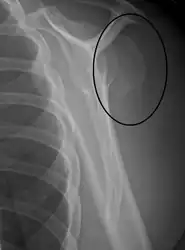

Closed shaft fracture in the middle of humerus